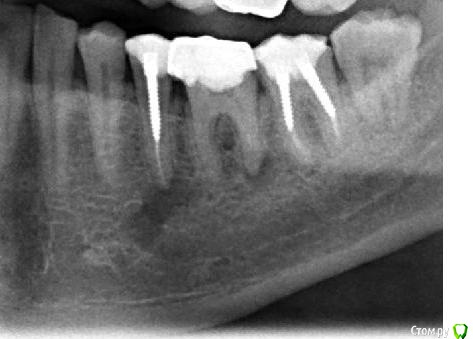

SergeySergey Опубликовано 16 октября, 2015 Поделиться Опубликовано 16 октября, 2015 Киста - что делать ? Заныла десна под 5 и 6 зубом, сделал рентген, результат - киста под 2-мя зубами 5 и 6 и еще киста между корнями у 6-ки.5 зуб болезненно реагирует на постукивания. Хирург и мой постоянный лечащий врач-терапевт говорят - нужно удалять два зуба и кисту, лечить не получится и обосновывают следующим:Проблема что 5 зуб со штифтом и вытащит штифт не возможно, а 6 проблемный в плане перелечивания, так как в канале есть инородное тело (возможно фрагмент инструмента), достать нереально а очаг как раз на верхушке этого корня, передние каналы 6 зуба тоже плохие (не видны), скорее всего не проходимы. Вероятно лечился резорцин-формалиновым методом и очень давно (1995-97 гг) Еще в другом месте врач-терапевт консультировал и говорит - не удалять а лечить все вопросы решаемые - штифт из 5-ки можно извлечь, если не извлечется штифт, то хирург доберется к кисте через челюсть, а 6-ку каналы можно вскрыть. и все вылечить за несколько месяцев и несколько посещений. Ваше мнение ? Что делать идти не к своему врачу а к тому который возьмется или удалять как говорить мой врач и хирург ? Ссылка на комментарий